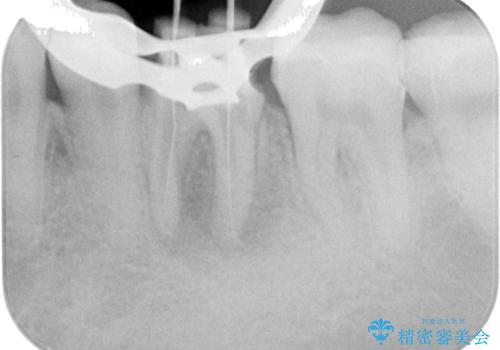

- 奥歯の歯肉から定期的に膿が出てくるとのことで来院された患者様です。

レントゲン写真などの診察を行った結果、根管治療が必要であったため、現在のクラウンを除去し、根管治療を行うこととしました。

4ヶ月後のレントゲンでは、病変の消退が認められました。